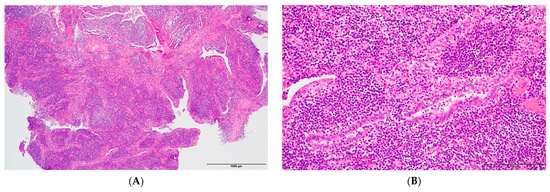

Well-Differentiated Papillary Mesothelial Tumor of the Scrotum with Suspicious Invasion

Well-differentiated papillary mesothelial tumor (WDPMT) is a distinct form of mesothelioma with low malignant potential and is mostly found in the peritoneal cavity. It consists of mesothelial cells with papillary structure and bland cytology. We report a rare case of WDPMT with suspicious [...] Read more.

Well-differentiated papillary mesothelial tumor (WDPMT) is a distinct form of mesothelioma with low malignant potential and is mostly found in the peritoneal cavity. It consists of mesothelial cells with papillary structure and bland cytology. We report a rare case of WDPMT with suspicious invasive foci in the tunica vaginalis. WDPMT with invasive foci is known to have a tendency for recurrence. Therefore, careful attention should be given to properly diagnosing and treating this rare entity. Full article